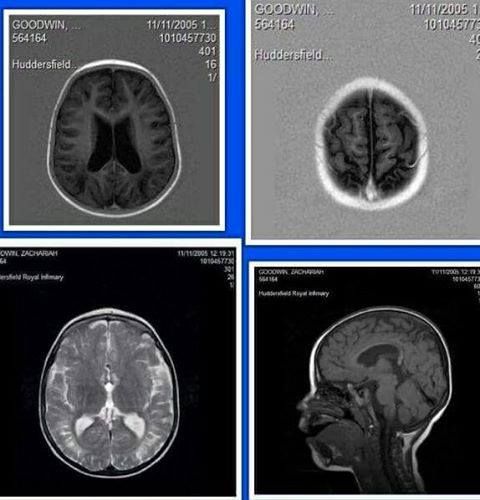

Nat was born a healthy 6lbs 6oz on the 25th June 2003 he was a very good baby and breastfed well, at the age of 2 weeks old Nat started having moments of been very unsettled and nothing much would settle him i took Nat to the doctors where i was told that i was been over fussy and Nat had nothing more than colic Nat continued to be unsettled but i put my trust into the doctor. 2 weeks later i had a doctors appointment myself we lived very close to the doctors so i changed Nat gave him a feed then laid him in his pram gave him a kiss and left him in the care of his father, whilst waiting for my doctors appointment i decided to ring Nat’s father and ask if everything was ok he said it was so i finally went and saw the doctor and walked back to our home. The walk home i was looking forward to just been back home relaxing and seeing Nat and his brother. I finally reached our home and opened the door what i walked back into was not the home i walked out of the home i walked into was one out of a nightmare and I just wanted to wake up, my oldest who was then nearly 4 years old was stood in the corner his little eyes wide like he had seen a ghost i asked him if he was ok he never moved then I just thought where is steven (my partner) he was sat in the chair i screamed at him asking what was going on and as calm has anything he said hi and ooh nothing all of a sudden i froze and thats when i saw Nat’s lifeless grey/blue body on the rug infront of the fire my world crumpled I remember grabbing Alex Nat’s older brother and Nat’s body and running to my friends home a few doors up. Has soon as i got there i rang 999 and was told how to do cpr on Nat finally the ambulance arrived it seemed like forever, we finally reached the hospital and i was asked so many questions i had no answers only that he was fine when i left him. Through the night at the hospital Nat had many tests he started having violent seizures and would be moved to a different hospital 2 hours away from where we lived and be placed in intensive care in a coma. Doctors did brain scans and sketal xrays we finally had an answer Nat had been violently shaken and thrown my world crashed around me i was only 19 years old with 2 children under 5 and now doctors and police were telling me that my youngest son had been violently abused and it was unlikely he would survive. It took 3 weeks for Nat’s father to finally admit to police he had assaulted Nat he told police IT FRUSTRATED ME, Nat’s father fractured Nat’s skull,broke 12 of his tiny ribs,broke both Nat’s clavicles,broke Nat’s tibia and fiba Nat also had bruising to his back and groin, Nat also had major bleeds to his eyes and brain,mri scans showed an old bleed which was 2 weeks old which would of been why Nat was so fussy at 2 weeks old he had a brain bleed not colic this doctor did appogise but the damage is already done. So today Nat is 14 years old and hes absolutely amazing he has a brain injury and widespread damage to his brain he functions at a 1 to 5 year old level in different areas he is developing very unevenly he has diplegia cerebral palsy, cortical vision impairment, servere learning difficulties,still in nappies,(diapers) communication difficulties and problems with memory but most of all hes a young man who never gives up despite everything hes gone through.